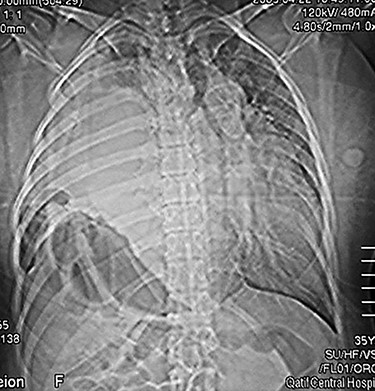

Chest x-ray (on arrival) showing a homogeneous opacity (the liver) occupying the right hemi-thorax with some bowel loops the right hemi-thorax with obvious mediastinal shift to the left side.

Her routine laboratory investigations including white cell count were normal. Electrocardiogram showed sinus tachycardia. Chest x-ray showed homogeneous opacity occupying the right hemi-thorax, and bowel loops were seen above the right chest with obvious mediastinal shift to the left side (Fig. 1). Abdominal computed tomography (CT) scan with contrast